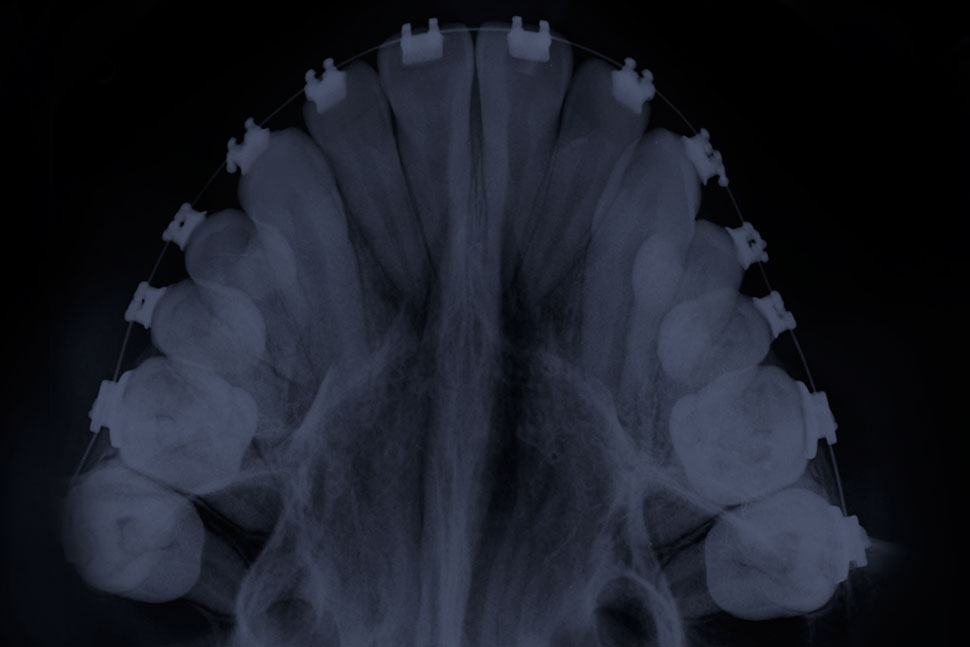

Radiografía Palatal u Oclusal

Captura todos los dientes superiores e inferiores en una sola toma.